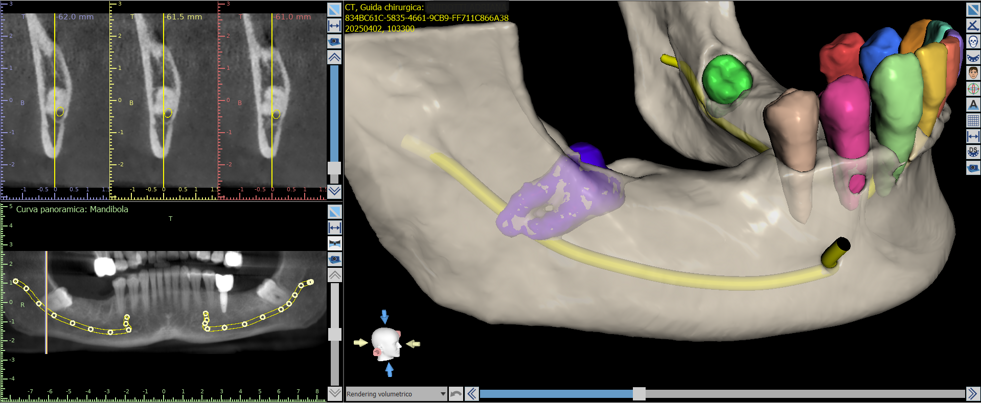

Il processo inizia con una tomografia computerizzata (CBCT), che fornisce un’immagine tridimensionale dettagliata delle arcate dentarie e delle strutture ossee. I dati vengono importati in software dedicati, dove il chirurgo può pianificare virtualmente l’intervento: scegliere la posizione, l’inclinazione e la profondità ottimali di ciascun impianto, valutando anche la densità ossea e la distanza da nervi o seni mascellari.

Una volta definito il piano chirurgico, si procede alla realizzazione di una dima chirurgica personalizzata, ottenuta tramite stampa 3D. Questa mascherina guida gli strumenti del chirurgo durante l’intervento, consentendo di inserire gli impianti nella posizione esatta prevista dal progetto digitale, senza necessità di ampie incisioni gengivali.